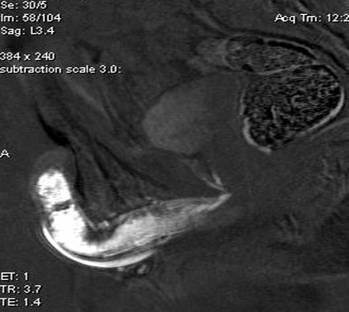

Очень редко половой член окостеневает по всей длине – описано менее 40 подобных случаев. Именно такой пациент стал героем статьи в новом номере журнала «Urology Case Reports». «Человеческий бакулюм» обнаружили случайно. 63-летний пациент, страдающий алкоголизмом, явился в отделение неотложной помощи из-за боли в левом колене после падения. Осмотр не выявил никаких осложнений, правда, мужчина жаловался на боль в половом члене. Пациенту сделали рентген органов малого таза… Тут-то и обнаружилась «обширная пластинчатая кальцификация» по всей длине пениса. Увы, пациент от дальнейшего обследования отказался, так что кроме рентгена, у врачей ничего нет.

Если бы не травма и не рентген, пациент, возможно, так бы и не узнал о своей уникальной особенности.